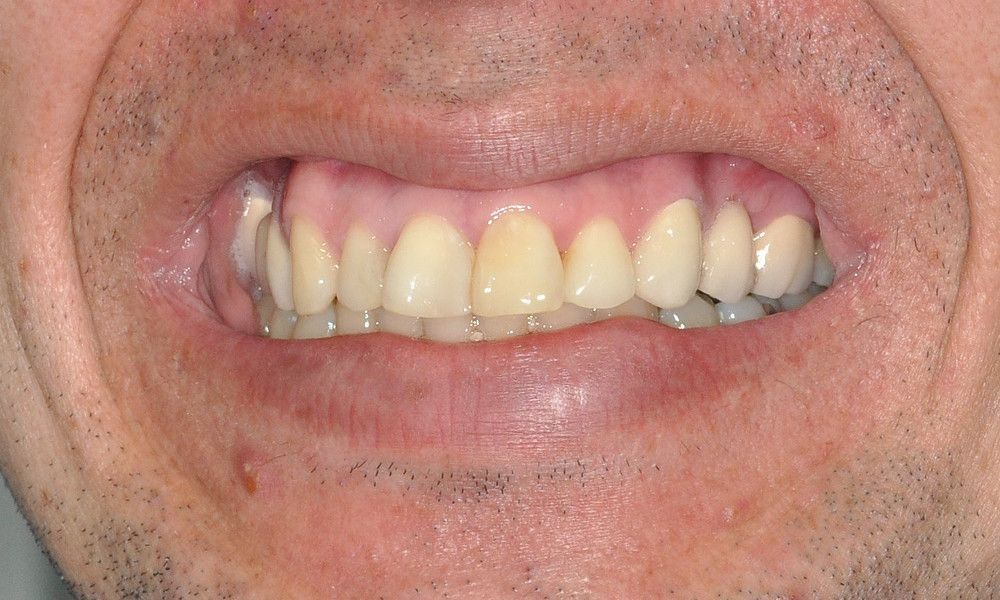

El estudio imagenológico evidencia una pérdida ósea severa en altitud y grosor, situación que complejiza la colocación de un implante. Se analizan alternativas de tratamiento y se opta por una vestibuloplastía mediante autoinjerto conectivo de mucosa palatina que se reposiciona sobre la zona del defecto óseo. Además se realiza retratamiento de ambas PFP, ahora en zirconia, por motivos estéticos y oclusales. Se realizan controles posteriores para evaluar la respuesta gingival a la vestibuloplastía.

Conclusiones: La ausencia de un diente no siempre es indicativo de implante. El tratamiento elegido debe tener las menores complicaciones, el mínimo daño, el máximo beneficio y un costo económico de acuerdo a la realidad del paciente. La PFP de zirconio y la vestibuloplastía son alternativas de tratamiento efectivas para la resolución de defectos óseos por ausencia dentaria en la cavidad oral.